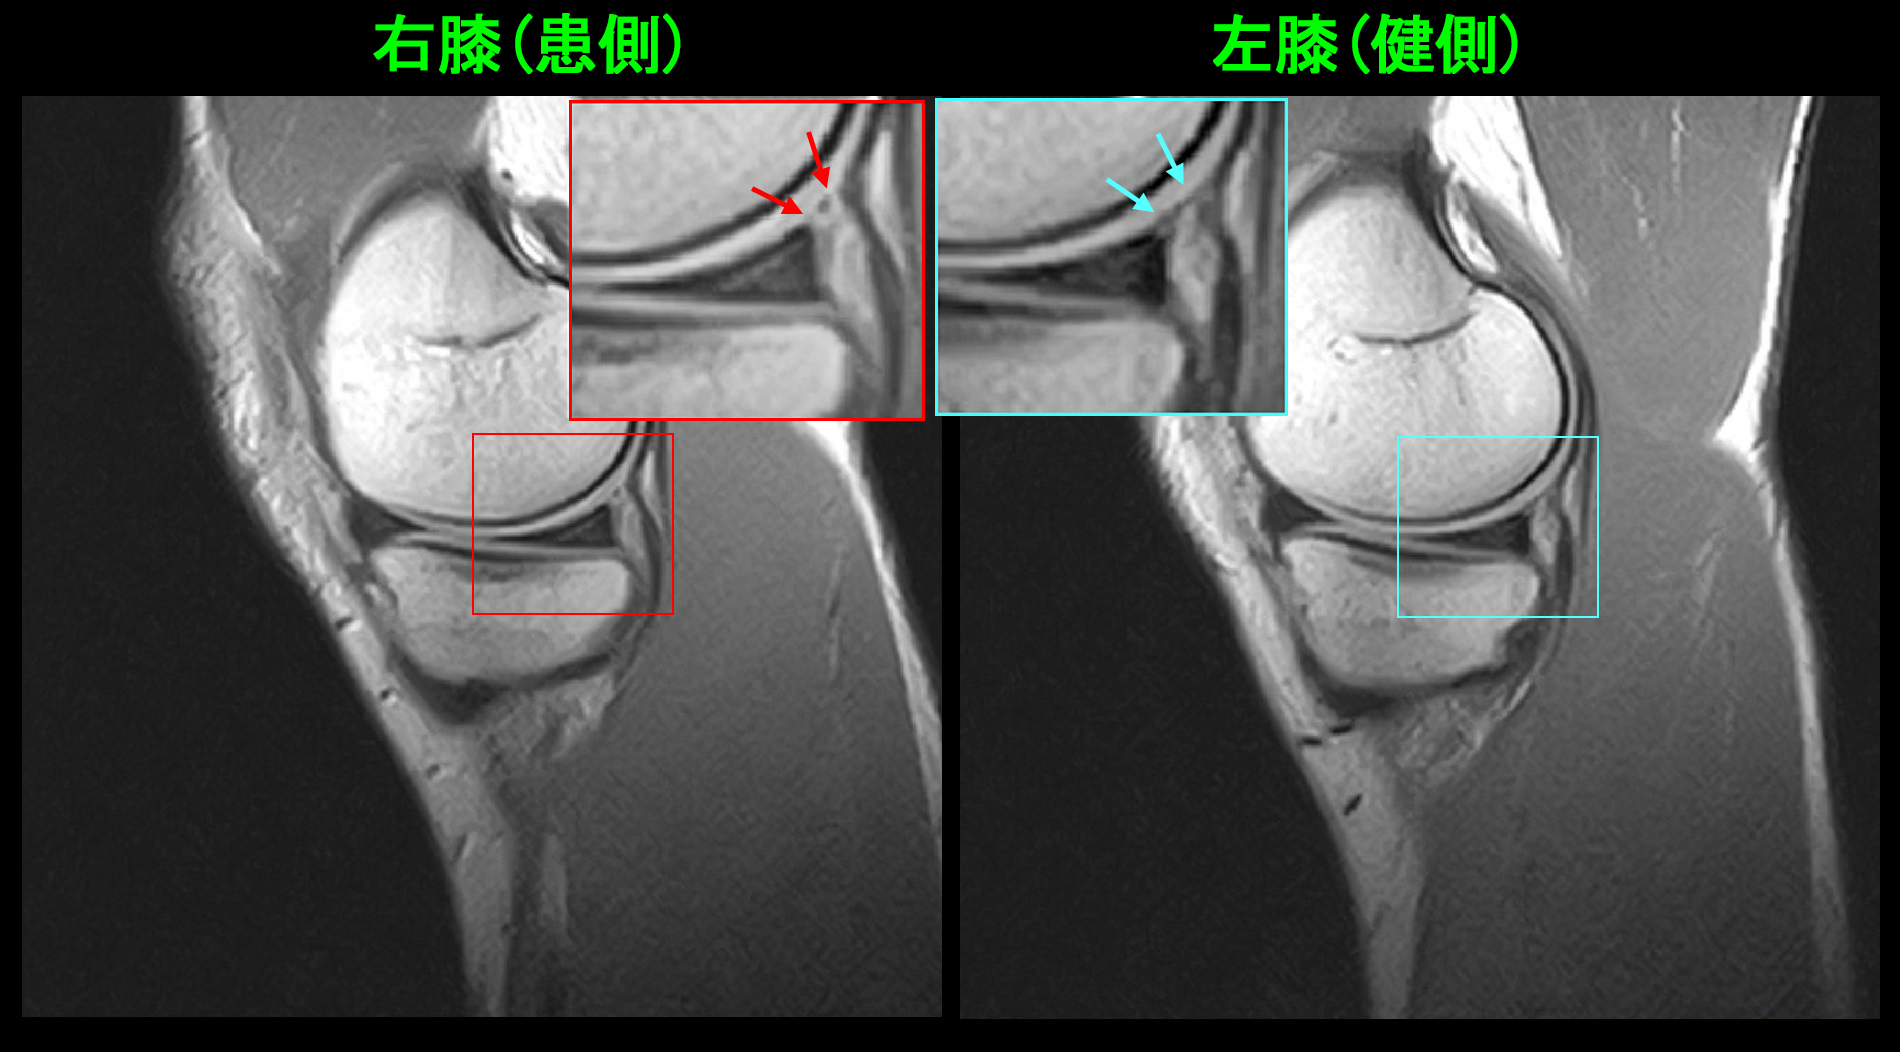

次の症例が服薬のみで半月板亜脱臼の痛みが治癒した患者さんです。17才のサッカー部の男子生徒です。令和7年12月27日から静岡遠征があり、初日の試合で全力疾走していて後方からスライディングされて前方に転倒し、右膝を捻挫し、以後は見学していたとのことでした。1月6日に当院を受診されました。1月10日のMRI検査(PDの冠状断)で右半月板の軽微な亜脱臼が確認されます。

17才男 MR1.jpgPD矢状断では内側半月板の関節包の接合部に軽度の損傷所見(左に比して接合部が白くなっています)が確認され、接合部損傷に伴う半月板亜脱臼と診断されました。

17才男 MR2.jpg

自転車で転倒の女子高生の経験と94才の女性の腰痛の経験から、しっかりとプレドニゾロンを処方する方針としました。鎮痛剤のロキソニン2錠とプレドニゾロン5㎎2錠と増量して1週間、2週目はロキソニン2錠とプレドニゾロン2.5㎎2錠で1週間の処方を行いました。この患者さんは5週後に手指痛で受診されましたが、右膝痛は治癒しサッカーには問題はないと報告してくれました。半月板亜脱臼も服薬で治療できる可能性があると知れた症例となりました。